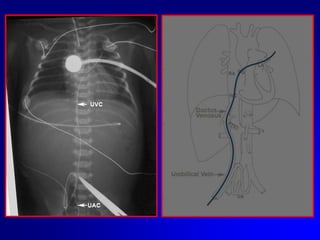

Eseguire sempre controllo radiografico o ecografico della posizione del catetere..

Se non è possibile passare il dotto venoso lasciare il catetere circa 2 cm dentro il piano cutaneo e valutare il ritorno ematico.

Il CVO può essere mantenuto per un tempo massimo di 14 giorni. Nei VLBW sarebbe preferibile rimuoverlo entro 7-8 giorniApplicare suzione lieve alla siringa.Se non vi è ritorno ematico vi può essere un coagulo sulla punta, quindi sfilare il catetere in aspirazione, rimuovere il cagulo e reinserire. Se vi è ritorno ematico, continuare ad inserire il catetere fino alla distanza stimata. Se il catetere incontra qualche ostruzione prima della distanza desiderata:Cause più comuniEntrato nel sistema portaleIncuneato in una branca intraepatica della vena ombelicaleRetrarre il catetere di 2-3 cm ruotarlo delicatamente e reinserirlo Se il catetere è nel circolo portale lasciare li il catetere; reinserire un altro 5–Fr nello stesso vaso. Una volta che il catetere è nella posizione giusta  si sfila quello in porta. Questa procedura ha successo nel 50% dei casi.

Eseguire semprecontrollo radiografico o ecografico della posizione del catetere..

Se nonè possibile passare il dotto venoso lasciare il catetere circa 2 cm dentro il piano cutaneo e valutare il ritorno ematico.

Il CVO puòessere mantenuto per un tempo massimo di 14 giorni. Nei VLBW sarebbe preferibile rimuoverlo entro 7-8 giorniApplicare suzione lieve alla siringa.Se non vi è ritorno ematico vi può essere un coagulo sulla punta, quindi sfilare il catetere in aspirazione, rimuovere il cagulo e reinserire. Se vi è ritorno ematico, continuare ad inserire il catetere fino alla distanza stimata. Se il catetere incontra qualche ostruzione prima della distanza desiderata:Cause più comuniEntrato nel sistema portaleIncuneato in una branca intraepatica della vena ombelicaleRetrarre il catetere di 2-3 cm ruotarlo delicatamente e reinserirlo Se il catetere è nel circolo portale lasciare li il catetere; reinserire un altro 5–Fr nello stesso vaso. Una volta che il catetere è nella posizione giusta si sfila quello in porta. Questa procedura ha successo nel 50% dei casi.